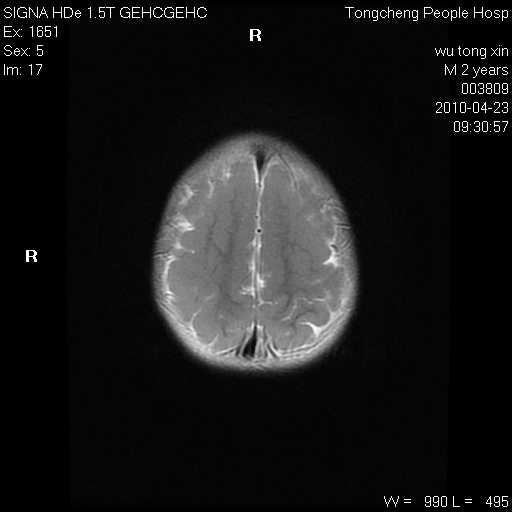

以下是引用赵物学在2010-4-25 12:43:00的发言:[br]巨脑回[br]侧脑室后角低密度影考虑hie或肾上腺脑白质营养不良?[br][br][本贴已被 赵物学 于 2010-4-25 12:51:28 修改过]

以下是引用gaoxiao在2010-4-25 16:54:00的发言:[br]巨脑回畸形。脑白质髓鞘化不良

以下是引用pujunzhi在2010-4-25 21:35:00的发言:[br]考虑 1双侧大脑皮质发育不良 2轻度脑积水 3双侧脑室后角旁片状长t1长t2信号,需继续观察,因为正常小儿此处脑白质的髓鞘化时间可以延迟到4-6岁,才显示正常。